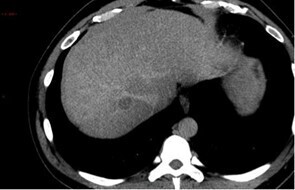

Le patient est finalement stabilisé hémodynamiquement, permettant son transfert en radiologie, et le scanner suivant est réalisé.

Question 11 - Sur ce scanner vous observez (une ou plusieurs réponses exactes) :

Le scanner retrouve de multiples masses intra-hépatiques infiltrantes. L’une d’entre elles, dans le segment V, est partiellement exophytique (bombant en sous-capsulaire) avec en son sein une flaque de produit de contraste. Par ailleurs, on retrouve une thrombose portale extensive de l’ensemble du système porte.

Au contact et le long de la gouttière pariéto-colique droite : un épanchement liquidien abondant, hétérogène, avec une composante spontanément hyperdense évocatrice de sang frais.

Le tout est donc évocateur, compte tenu par ailleurs des antériorités du patient, d’une progression de la maladie avec un CHC infiltrant bi-lobaire, rompu dans la cavité péritonéale avec saignement actif.